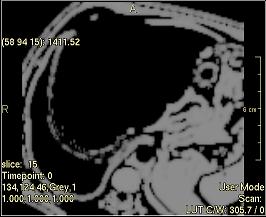

No Filter

The output image is an identical copy of the input image.

../../../Modules/ML/MLFilter2/mhelp/Images/TextureFilterImages/original.jpg